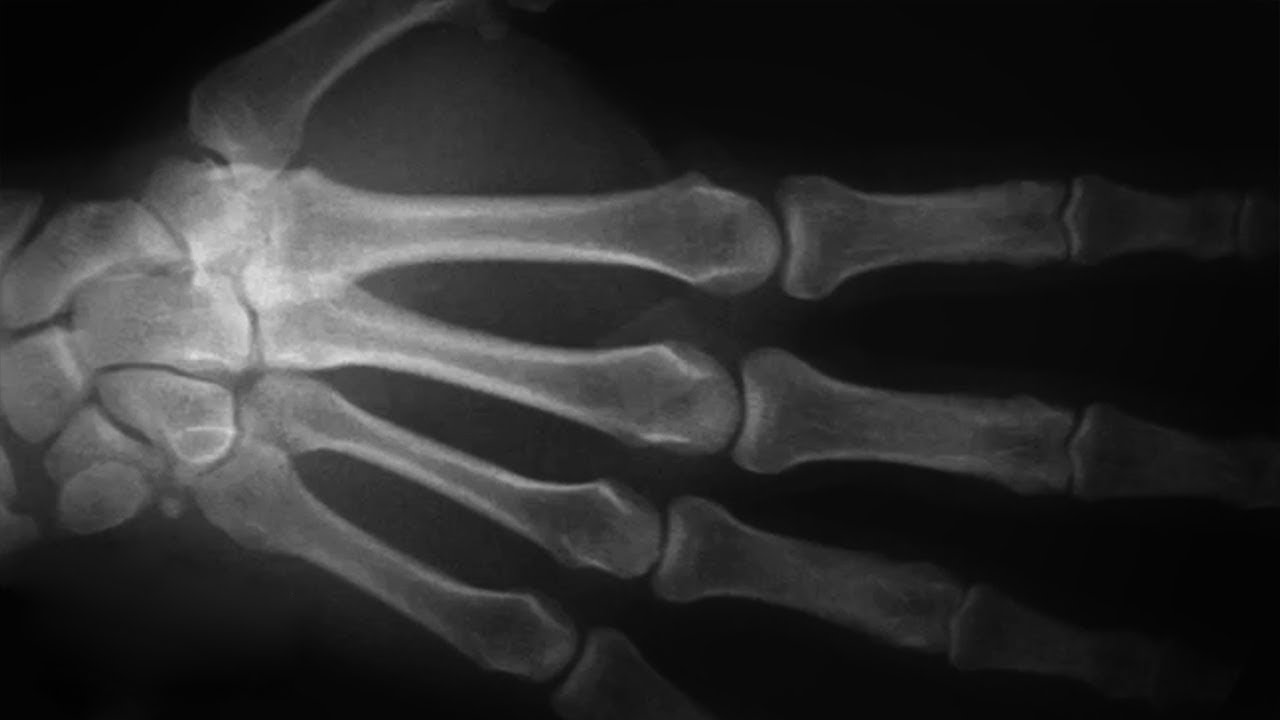

Строение и функции кисти

Если строение кисти руки рассматривать с точки зрения анатомии, то будет любопытно узнать, что это целый конгломерат из 32 косточек и костей, скрепленных между собой прослойками мышц и сухожилий, которые помогают верхним конечностям выдерживать большие нагрузки.

В кисти 3 отдела:

Пясть состоит из 5, а запястье из 8 тонких трубчатых, зависимых друг от друга костей. Они неразрывно связаны с пальцами, каждый из которых имеет три фаланги:

- проксимальную;

- среднюю;

- дистальную.

Исключение составляет большой палец, у которого отсутствует средняя фаланга.

Пальцы достаточно подвижны, точны в движениях и функциональны. Они состоят из трубчатых укороченных костей с подвижными суставами и целой сетью средних и мелких сосудов. Суставы фаланг имеют форму, исключающую боковые движения, но не препятствующую сгибанию и разгибанию.